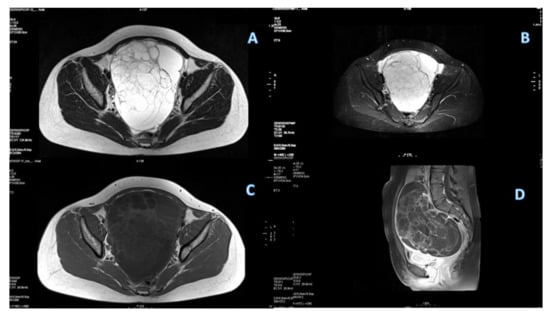

Characterization of Primary Mucinous Ovarian Cancer by Diffusion-Weighted and Dynamic Contrast Enhancement MRI in Comparison with Serous Ovarian Cancer